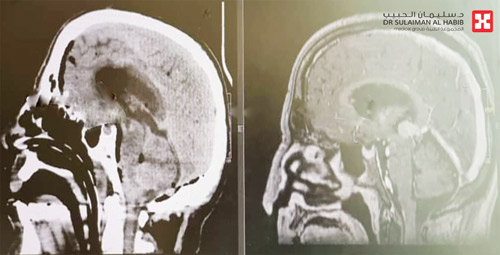

نجح مستشفى الدكتور سليمان الحبيب بالقصيم في إجراء عملية دقيقة والمريض في وضعية الجلوس، تم فيها استئصال ورم نشأ بين عنق الدماغ ومراكز الوعي، وكان الورم متداخلاً مع الخلايا بحجرة الدماغ الثالثة. وتسبب الورم في مجموعة أعراض حادة للمريض تفاقمت مع مرور الوقت وانتهت به إلى ملازمة العناية المركزة.

وقال د. ناجي مسعود استشاري جراحة المخ والأعصاب، رئيس الفريق الطبي المعالج أن معاناة المريض بدأت بأعراض كالصداع والدوار، قبل أن تبدأ في التطور ويصاب بالحول والزغللة، ومن ثم فقدان القدرة على المشي والنوم. وقد تم إدخاله العناية بأحد المستشفيات ثم حول إلى مستشفى الدكتور سليمان الحبيب. وقد خضع المريض لفحوصات طبية دقيقة وكاملة للدماغ وأظهرت النتائج وجود ورم بين عنق الدماغ ومراكز الوعي متداخل مع الخلايا بحجرة الدماغ الثالثة، ومتصل بشبكات شريانية ووريدية كبيرة، ويضغط على مراكز الحركة والوعي والتنفس والأوردة والشرايين المهمة في عنق الدماغ.

وأضاف د. مسعود أنه تم عرض الحالة مع نتائج الفحوصات على استشاريي القلب والتخدير لتقييمها وقد توصل الفريق الطبي لخطة علاجية، ومن ثم أخضع المريض لعملية دقيقة وهو في وضعية الجلوس، وتم الدخول بفتحة خلف الجمجمة، مع استخدام تقنيتي المايكروسكوب ومراقبة الأعصاب أثناء العملية، والوصول إلى موضع الورم الذي كان قد بدأ في النزف، بين الدماغ وغشاء المخيخ، وجرى فصله عن الأعضاء الحساسة الملاصقة له بدقة فائقة، ومن ثم إزالة الورم بالكامل مع المحافظة على سلامة المراكز الحيوية المحيطة والأوعية الدموية، كما تم زرع أنبوب لتصريف السائل الدماغي، بعد انسداده بفعل الورم. وقد استمرت العملية مدة (7) ساعات متصلة، وتكللت جهود الفريق الطبي ولله الحمد بالنجاح التام، وبعدها تم التحقق من علاماته الحيوية وتحريره من التنفس الصناعي ثم نُقل إلى العناية المركزة التي بقى بها لمدة «5» أيام تحسنت خلالها حالته، ثم حُول إلى غرفة التنويم حيث أمضى «5» أيام أخرى، استعاد خلالها القدرة على المشي، كما تراجعت حدة الأعراض الأخرى، مع العلاج الطبيعي والرعاية الطبية الحثيثة، ثم غادر المستشفى وهو يمشي على قدميه بحالة صحية جسدية ونفسية جيدة، ولاحقاً تخلص من كافة الأعراض، ولم يصب بأي مضاعفات عصبية، ووصف د. مسعود الحالة بالمعقدة، مضيفاً أن نجاحها يؤكد كفاءة وتمرس الفريق الطبي والإمكانيات والتجهيزات المتقدمة التي يحظى بها المستشفى.